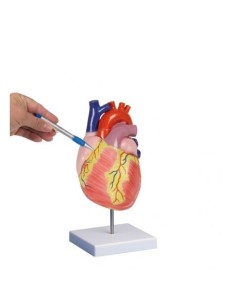

Des modèles anatomiques détaillés pour tous les besoins

Du crâne en 22 parties à verrouillage magnétique aux modèles de colonne vertébrale, des modèles d'articulation aux modèles de cœur, chaque pièce de notre collection est conçue pour une immersion totale dans l'étude de l'anatomie humaine. Nos modèles, réalisés à partir de scans d'os réels, garantissent une expérience tactile authentique et une fidélité de poids presque identique aux originaux.

Indispensables aux étudiants comme aux professionnels, nos modèles anatomiques sont des outils pédagogiques qui permettent d'observer les structures anatomiques avec précision, en évitant les dissections ou les études invasives. Ils sont également utiles pour expliquer les pathologies aux patients, ce qui rend la communication plus efficace et permet de gagner un temps précieux.